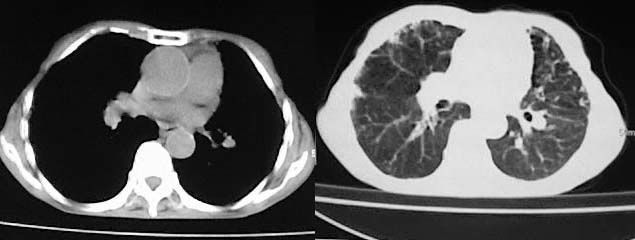

以下是引用有风的日子在2008-5-2 12:13:00的发言:[br][emb10][br][br]肺ca?有病理支持吗?[br][br]我看更象是肺tb并支扩、间质性肺炎。最好拿个病理结果来,不然这点影像资料诊断肺ca是难以服人的![br][br]至于主动脉瘤的诊断问题,国外认为≥4.0cm就可诊断了,国内对此诊断标准更为严格。患者升主动脉明显增粗,即>4cm。你诊断个升主动脉扩张并不为过!

以下是引用zjzjr在2008-5-2 14:39:00的发言:[br]支持双侧继发型肺结核,左侧胸膜肥厚,慢性支气管炎伴间质纤维化.